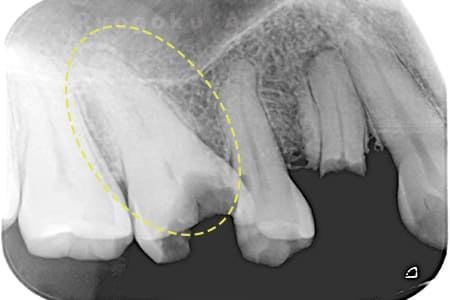

Case10

- 原因

- 慢性根尖性歯周炎並びに重度歯周病の併発

- 治療期間

- 約半年

- 治療内容

- マイクロエンド並びに歯周再生療法

- 治療費用

- 約298,000円

左下の違和感が消えず、数医院を周り、抜歯と判断され、治療を断られた患者様です。十分な説明の下、根管治療並びに歯周再生療法の話をし、同意を得て、行いました。術後経過も良好で、抜歯をせずに歯を残すことができました。

<リスク・副作用>

術後は痛み、腫れ、痺れなどの副作用が生じる場合があります。症状が再発する可能性があります。